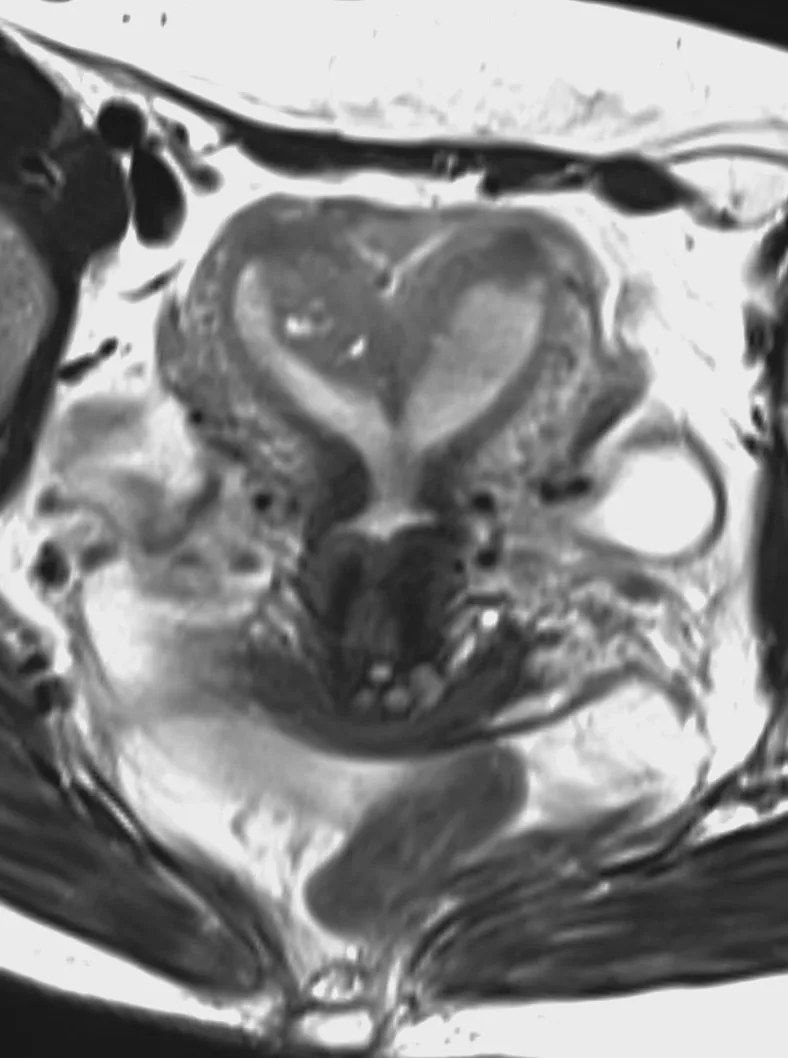

Наконец-то я увидел это воочию! Киста полости Верги, промежуточного паруса, осложнённая гидроцефалией. Из анамнеза: Низкое артериальнео давление, нарушение речи, затуманенное сознание, головная боль, головокружение, в 1989 году перенёс менингит.

А Вы видали такое? Я впервые вижу, раньше только читал в литературе.